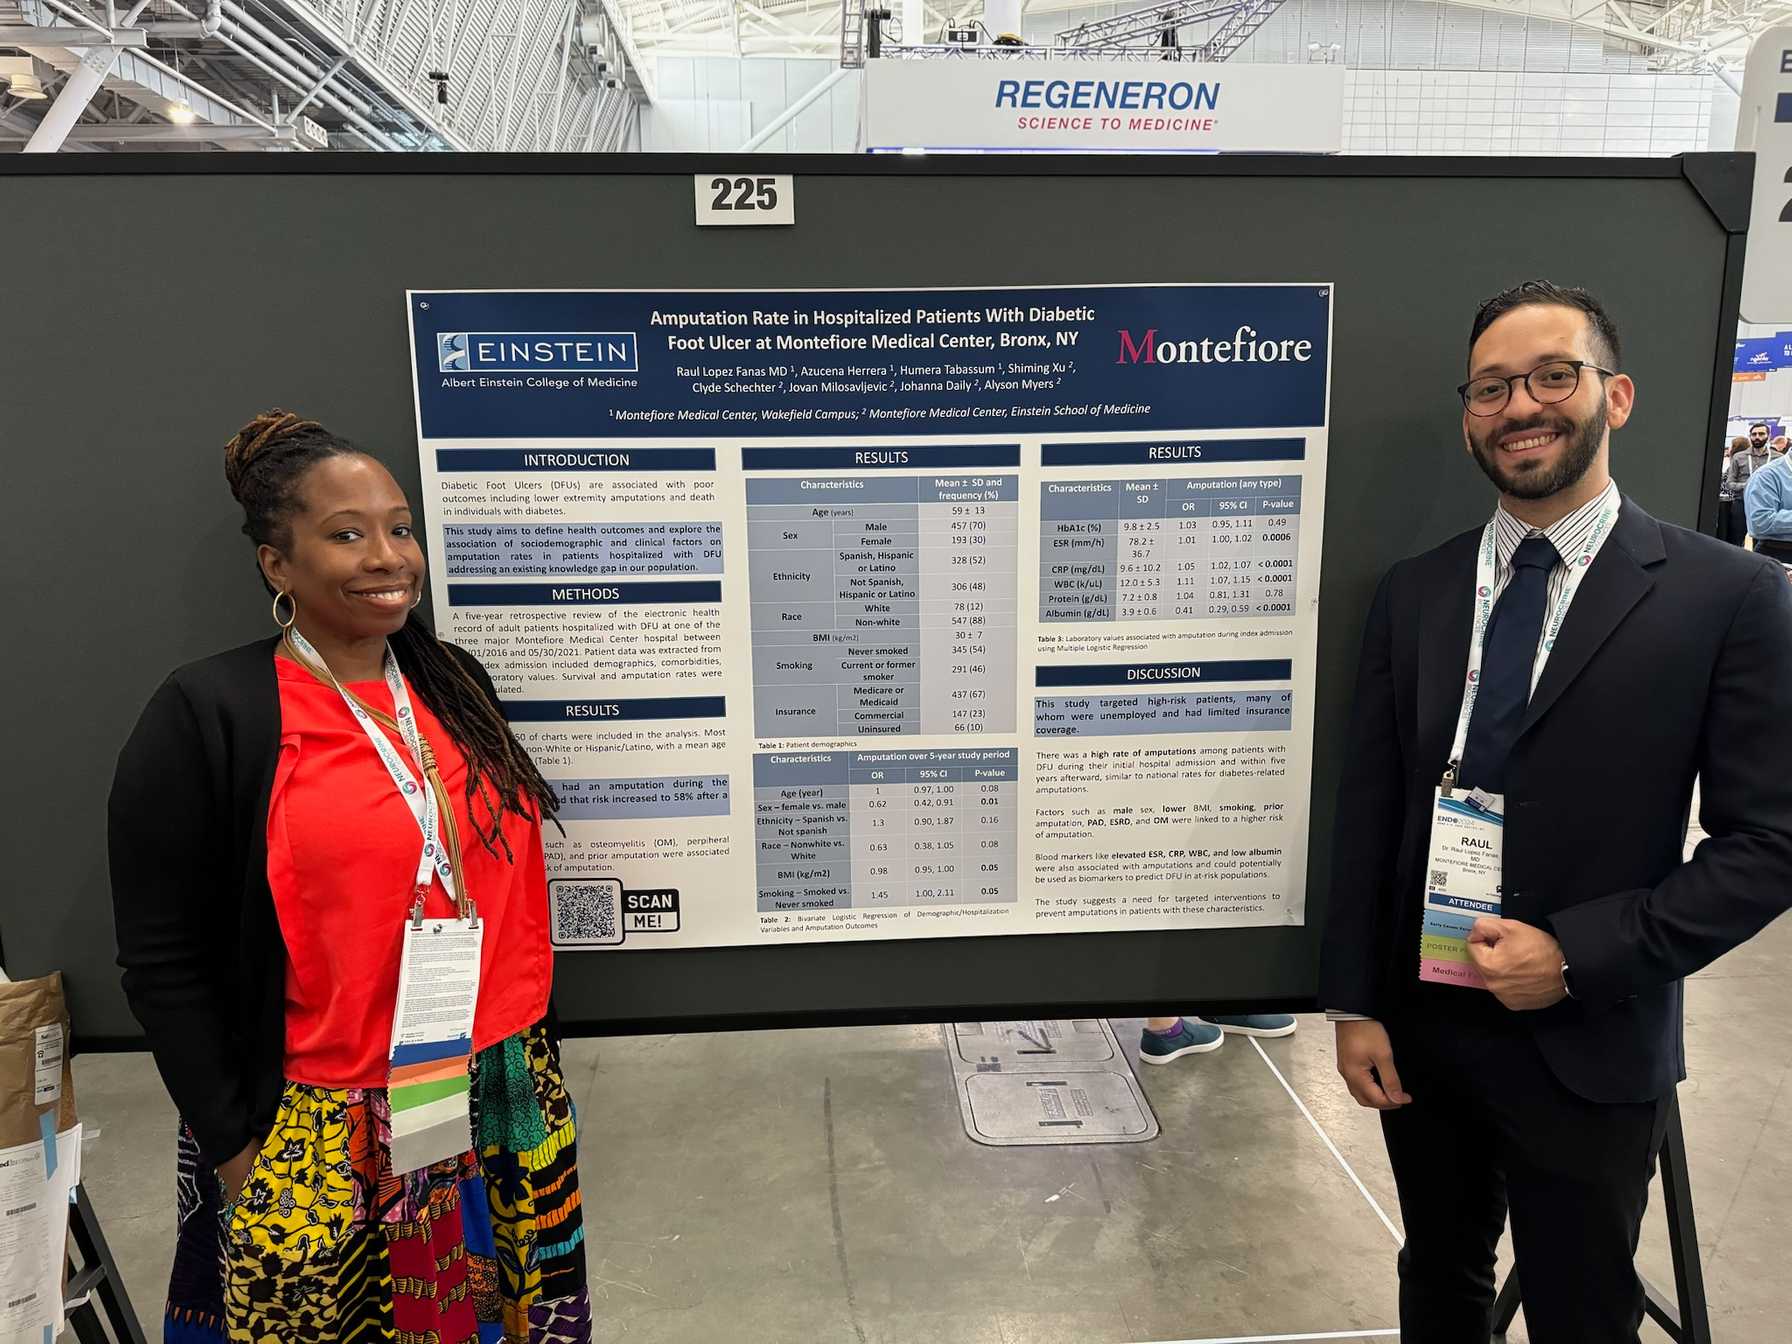

- Contribution to medical literature through the preparation of case reports, abstracts, posters and manuscripts to present in local, regional and national conferences and forums

Endocrinology Fellows become familiar with research in their first year under the stewardship of Sofiya Milman, MD, Associate Program Director for Research. Depending on their experience and future career interests, fellows can choose to initiate their own research project or join an ongoing project, working with helpful and experienced mentors. Fellows also participate in didactic seminars on research methodology, scientific writing and quality improvement studies. During their training, fellows gain valuable research experience, and most contribute to their field by presenting their findings at regional or national conferences or in a manuscript.